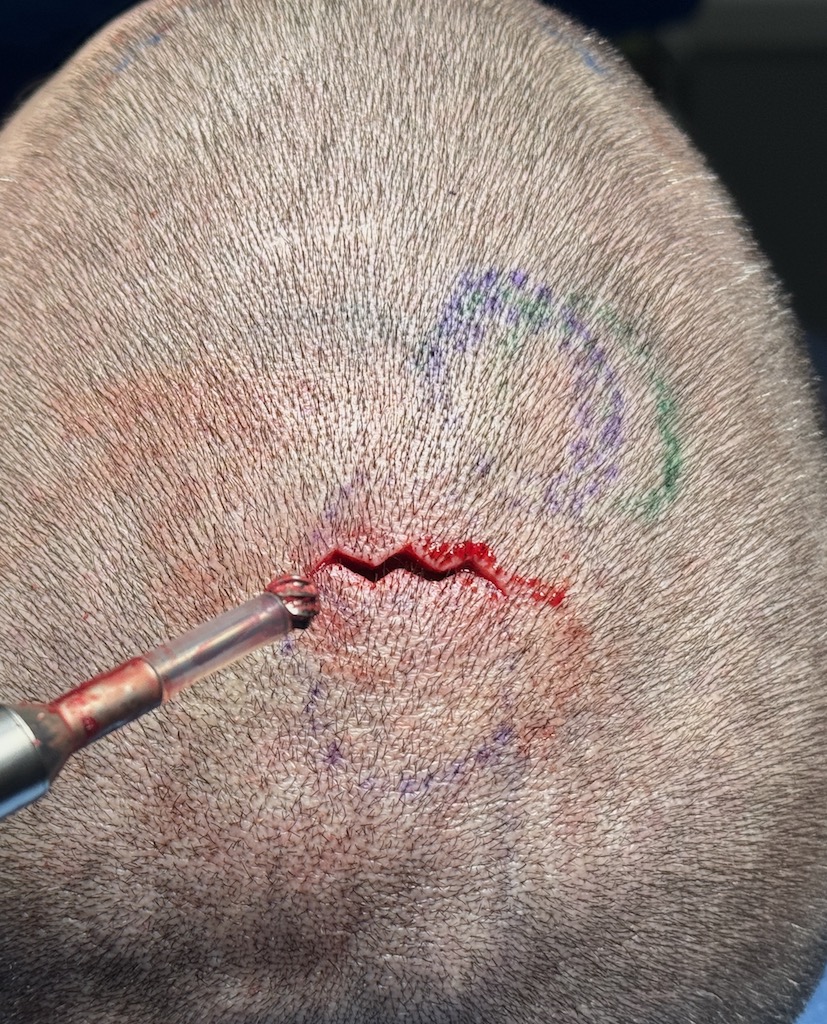

Desire for reduction of prominent occipital knob deformity.

Intraoperative result from occipital knob skull reduction through a direct small scalp incision.

Desire for reduction of prominent occipital knob deformity.

Intraoperative result from occipital knob skull reduction through a direct small scalp incision.